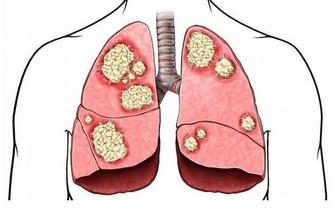

4、肺部有毒:合谷穴

肺部有毒的體現之一即是呈現便秘景象。